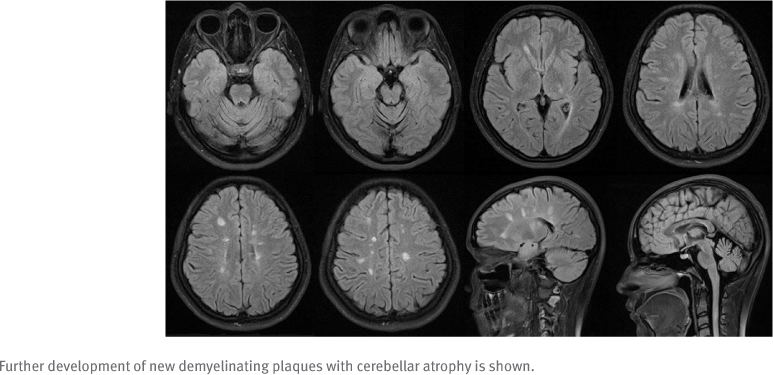

The proband is a 25-year-old woman who received a diagnosis of relapsing-remitting MS at age 13. The diagnosis was based on dissemination in time and space and fulfillment of the McDonald criteria for the diagnosis of pediatric MS. She had multiple attacks involving the sensory, motor, cerebellar, and spinal cord regions. Magnetic resonance imaging (MRI) of the brain and spinal cord demonstrated multiple classical periventricular white matter demyelinating plaques with Dawson fingers and spinal cord involvement (FIGURE 1). She was started on weekly interferon beta (IFNβ)-1a at a dose of 30 μg per intramuscular injection. Unfortunately, her disease progressed both clinically and radiologically for 7 years, despite her adherence with interferon therapy (FIGURE 2). She had 1 to 4 relapses per year, which necessitated treatment escalation for which she was switched to fingolimod 0.5 mg once daily, with good control of her disease during the past 2 years. She has a positive family history of MS in her sister, who is 31 years old and was diagnosed at age 28, as well as her brother, who is 21 years old and was diagnosed at age 17 (FIGURE S1, which is published in the online version of this article at ijmsc.org). Her sister and brother used interferon therapy for 1 and 2 years, respectively, with multiple relapses and deterioration of Expanded Disability Status Scale scores and gait. They were shifted to fingolimod 0.5 mg once daily, with excellent response and improvement in Expanded Disability Status Scale scores. Their brain MRIs showed classical multiple periventricular demyelinating lesions, and they did not have cerebellar atrophy. The parents were not consanguineous, and none of the siblings had genetic diseases that run in the family, including cystic fibrosis, glucose-6-phosphate dehydrogenase deficiency, familial Mediterranean fever, or any other genetic diseases.

Magnetic Resonance Image of the Brain, Fluid-Attenuated Inversion Recovery Sequencing, at Age 24

Although the cause of MS is still unknown, neurologic symptoms are thought to be immune-mediated tissue damage directed against myelin antigens. This will result in demyelination with the loss of axons and cell bodies that lead to progressive neurologic symptoms. Patients with MS typically experience symptoms such as focal weakness, monocular blindness, diplopia, sensory and coordination dysfunction, and muscle fatigue.12 In a study by Andrijauskis et al,11 pyramidal and brainstem lesion symptoms were more predominant early in the disease course in patients with MS with a first-degree family member than in the control group with no family history. In addition, cognitive dysfunction, headaches, and back pain were more common in familial MS. Furthermore, patients with familial MS present with more exacerbations annually, especially in the first year of disease activity, with a subsequent decline in the number of these attacks in the following years. Lesions in the brainstem and cerebellum are more commonly observed on MRIs of patients with familial MS. For all the previously mentioned reasons, and because of changes that occur in the hypothalamic-pituitary–adrenal axis, the degree of disability was higher in patients with familial MS.11 In the present patient, striking cerebellar atrophy was obvious on neuroimaging, which is a subject of research that needs explanation. The present patient was scanned using the same MRI machine and identical protocols at all visits. The MRI was performed regularly every 6 to 12 months during patient follow-up. Unfortunately, the quantification of cerebellar atrophy is not routinely performed in the neuroradiology department at our institution.